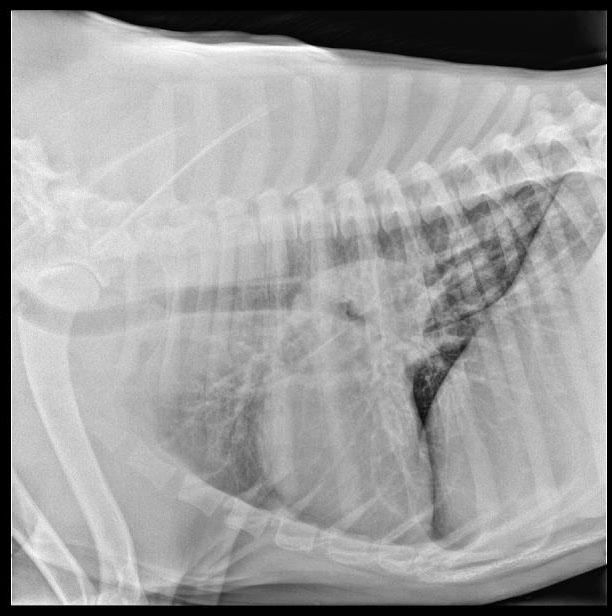

The patient is a canine Mastiff, male, 1 year old who was presented for surgery for the eye, however physical exam revealed muffled heart sounds. Radiographs revealed mass at the heart base.